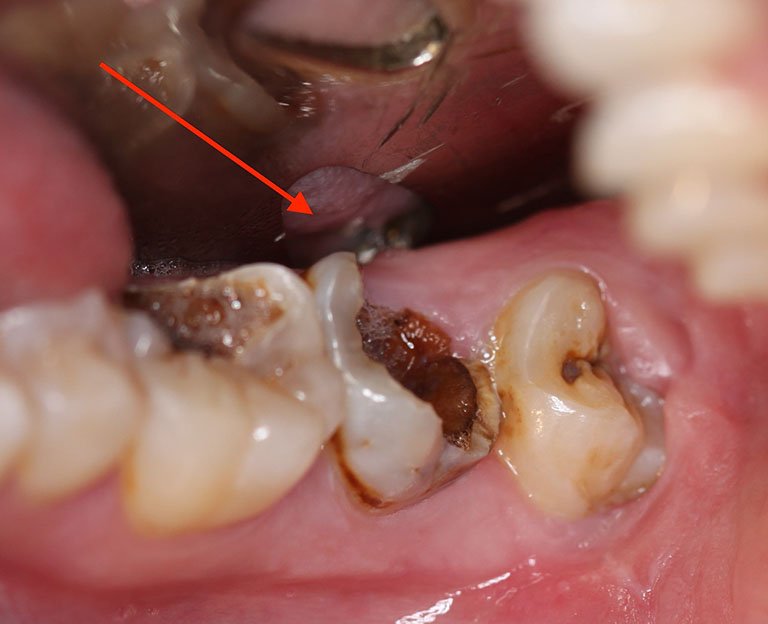

Tuỷ răng bị tổn thương chủ yếu do sâu răng, nếu không được điều trị sớm sẽ gây ra những biến chứng rất nguy hiểm. Trong đó, một số bệnh lý thường gặp phải điều trị cấy tuỷ răng bao gồm:

Viêm tủy không hồi phục

Ở giai đoạn này, viêm tuỷ làm tổn thương tủy hoàn toàn, răng không thể phục hồi về tình trạng ban đầu. Người bệnh sẽ phải trải qua những cơn đau dữ dội khi ăn thức ăn quá lạnh hoặc quá nóng. Cơn đau này sẽ kéo dài và có thể lan sang các vùng khác.

Viêm tủy cấp

Viêm tuỷ cấp tạo ra các cơn đau kéo dài, đau cả khi đang người bệnh đang thư giãn, nghỉ ngơi. Cơn đau sẽ khó chịu và đau đớn hơn khi người bệnh ăn những món quá lạnh, quá nóng, khi thức ăn rơi trúng vùng răng đang bị viêm nhiễm.

Những cơn đau có thể xuất hiện từng đợt hoặc liên tục khiến người bệnh vô cùng khó chịu, làm giảm chất lượng cuộc sống. Bệnh sẽ rất nghiêm trọng khi tuỷ răng sinh mủ.

Hoại tử tủy

Lúc này tủy răng không còn nguyên vẹn, nê người bệnh thường không còn cảm giác đau hoặc khó chịu. Để lâu hơn, hoại tử có thể dẫn đến áp xe, tụ thành mủ bên trong răng và các mô xung quanh răng rất đau đớn. Lúc này, nguy cơ cao sẽ lan sang các khu vực khác trong khoang miệng.